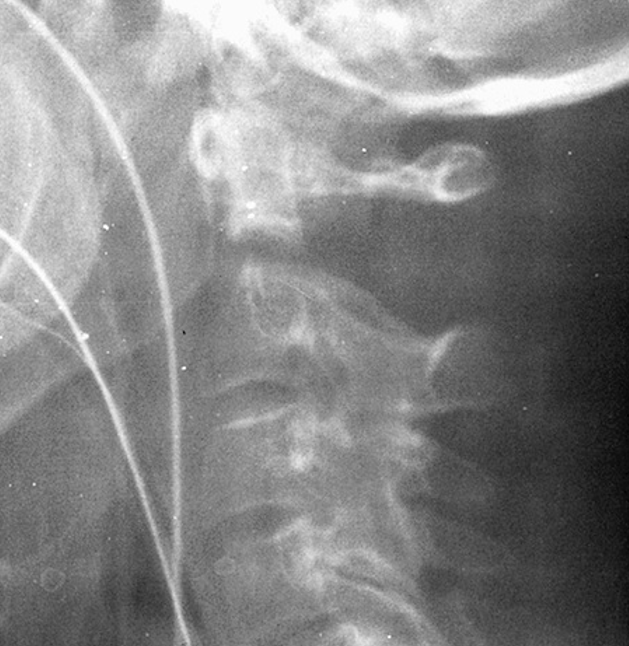

Type 2

Fracture of base of odontoid process

- most common type

- > 50%

Type II Dens Fracture

Issue

Stability

Union

Risk factors for nonunion

- 69 patients with acute type II fractures treated with halo vest

- union 32/69 (46%)

- nonunion associated with:

- fracture gap > 1 mm

- posterior displacement > 5 mm

- delay in treatment > 4 days